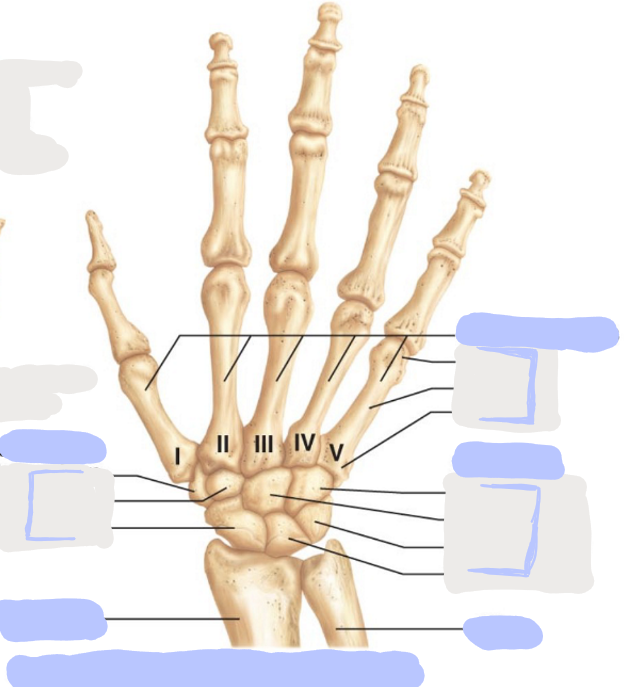

What is this picture of?

Posterior View of the Right Hand

What is here?

Where is the Ulna?

What is here?

Where is the Radius?

What is here?

Where are the Metacarpals?

What is here?

Where are some of the Carpals?

What is here?

Where are some of the Carpals?

How many carpals are there?

8

How many metacarpals are there?

5

How many phalanges are there?

14